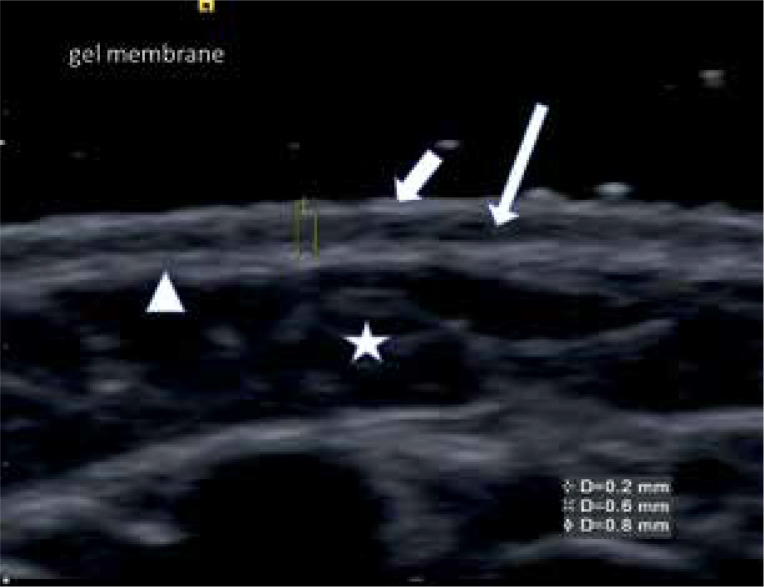

Material and methods: This cross-sectional study included children aged 4-18 years with asthma and/or allergic rhinitis. Participants were divided into three groups: healthy controls (n = 50), patients sensitized to house dust mites (n = 60), and patients with negative house dust mite tests (n = 48). The thickness of the dermis layers of the skin was measured at the cubital fossa using an ultrasound.